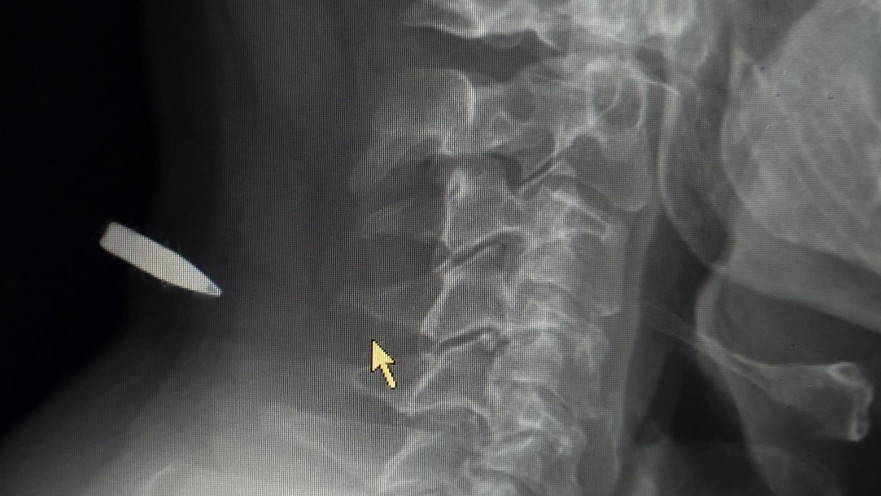

צילום הרנטגן של הכדור שנתקע בצווארו

צילום הרנטגן של הכדור שנתקע בצווארו | צילום: באדיבות המצולם

לדבריו, גם במהלך הפינוי נשאר רגוע: "בדרך הם לקחו לי מדדים, ואני כל הזמן אמרתי להם שהכול רגיל. כשהגענו לחדר ההלם כבר חיכו הצוותים. עשו לי צילום וראו שהכול בסדר. הרופא שלף את הקליע בקוטר 5.56 והוא רק הרדים טיפה את המקום. הכול היה מהיר ומדויק. בתוך שעות בודדות הכול נגמר".